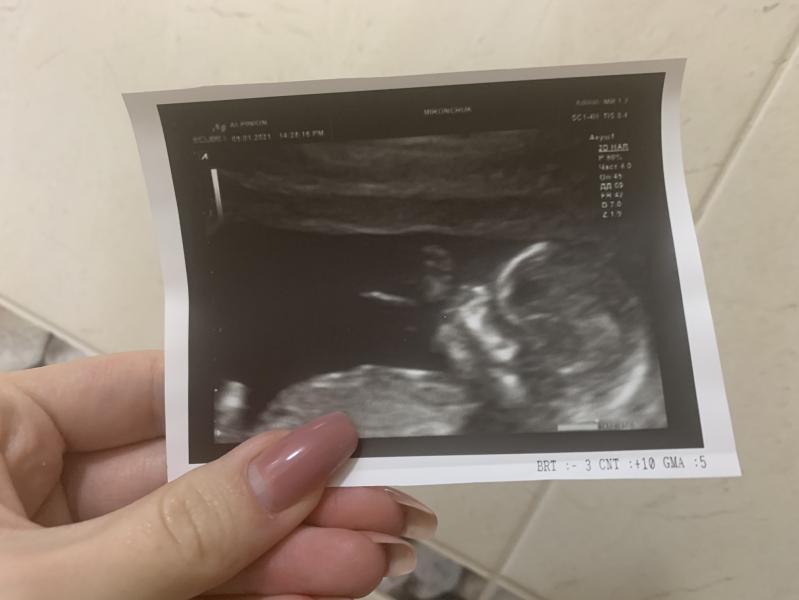

Пузожитель передаёт всем привет 😌

1-й скрининг (29.12.20 - 12 недель) позади , предположили девочку. После короны с темпой делала внеплановое УЗИ, предположили мальчика (вроде как пипку увидели). 😬

Думаю мальчик все же)))

Если правильно поняла, чуть выше головы рука, смотрю одного гинеколога-мужчину в инсте, он постоянно сравнивает узи девочек и мальчиков, говорит, что это типичная поза для мальчика, держать/класть руку на/к лицу😄

Кстати , сын , первый ребёнок мой, тоже руку все время подкладывал под лицо , даже родился так , с рукой у лица, что эпизио пришлось делать 😅